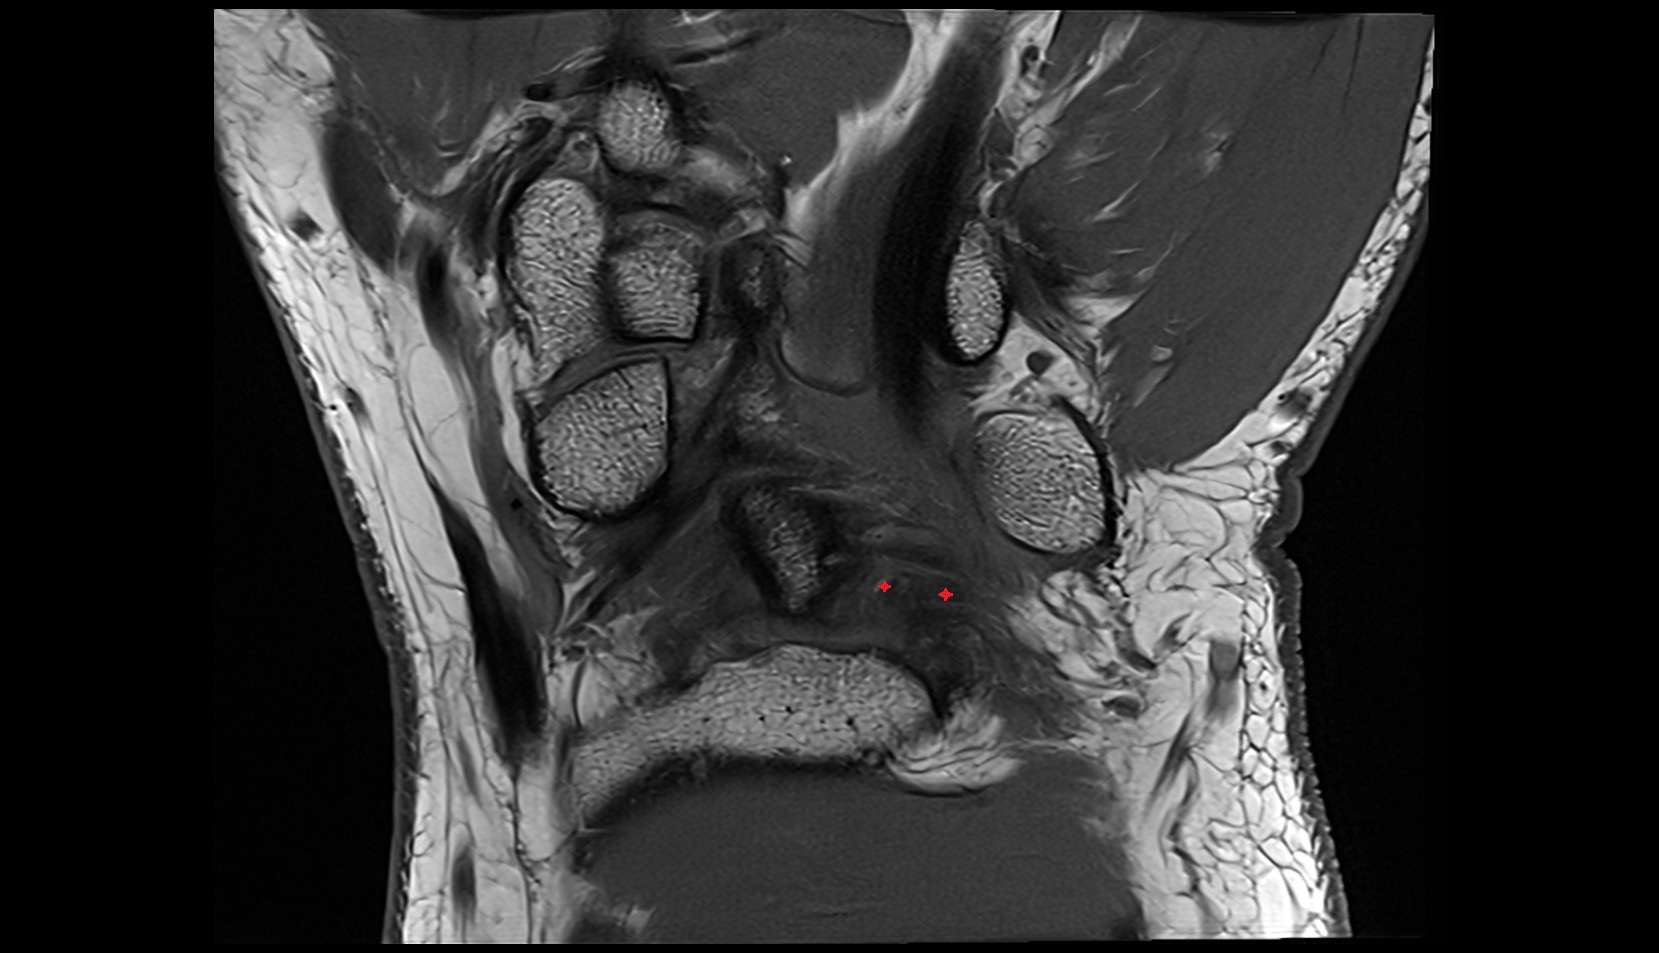

- Anterior cruciate ligament

- Posterior cruciate ligament